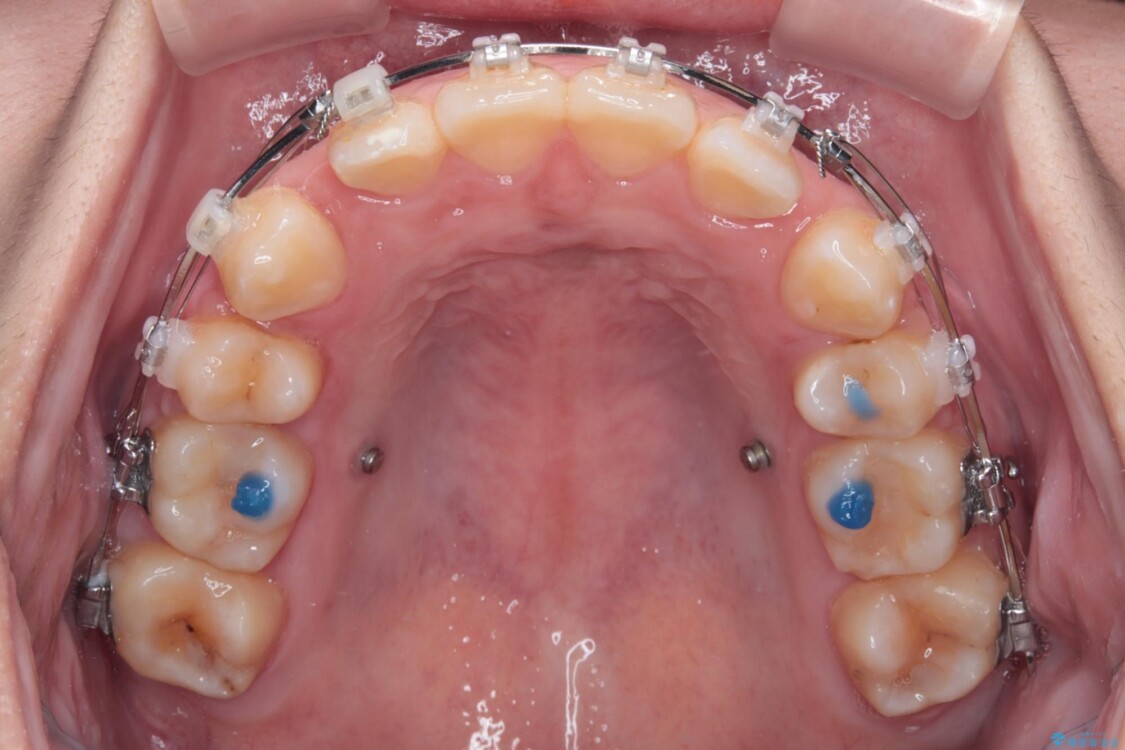

治療途中

• 転勤でも安心して治療継続 抜歯スペース閉鎖と深い噛み合わせ改善のワイヤー矯正 治療途中画像